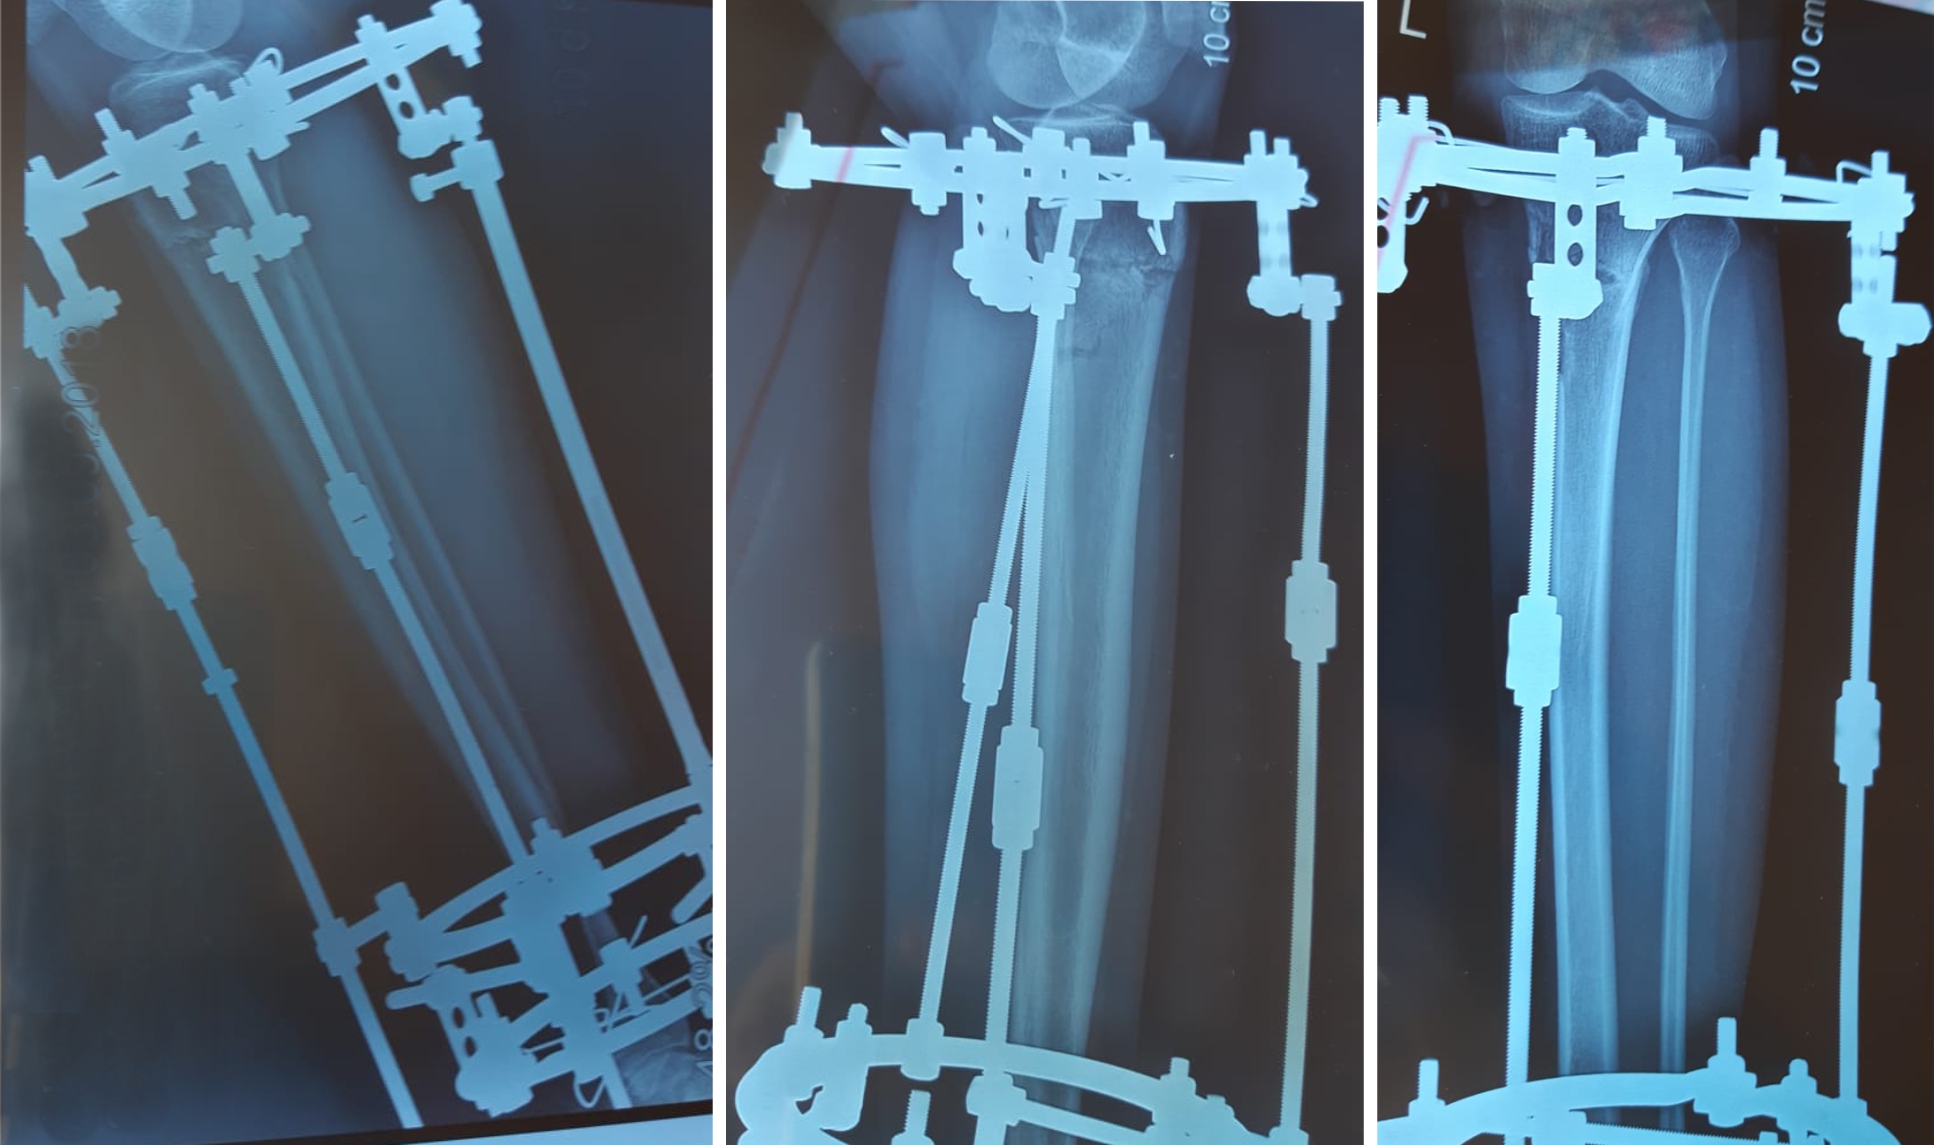

Исходник - Тараз, 35 лет.

Дата операции 04.07.2018г.

перед крутками.

В процессе круток.

У пациентки имеется Ротация.

Рентген в 90 дней.

Дата снятия аппаратов 16.10.2018г.

Срок сращения - 102 дня.